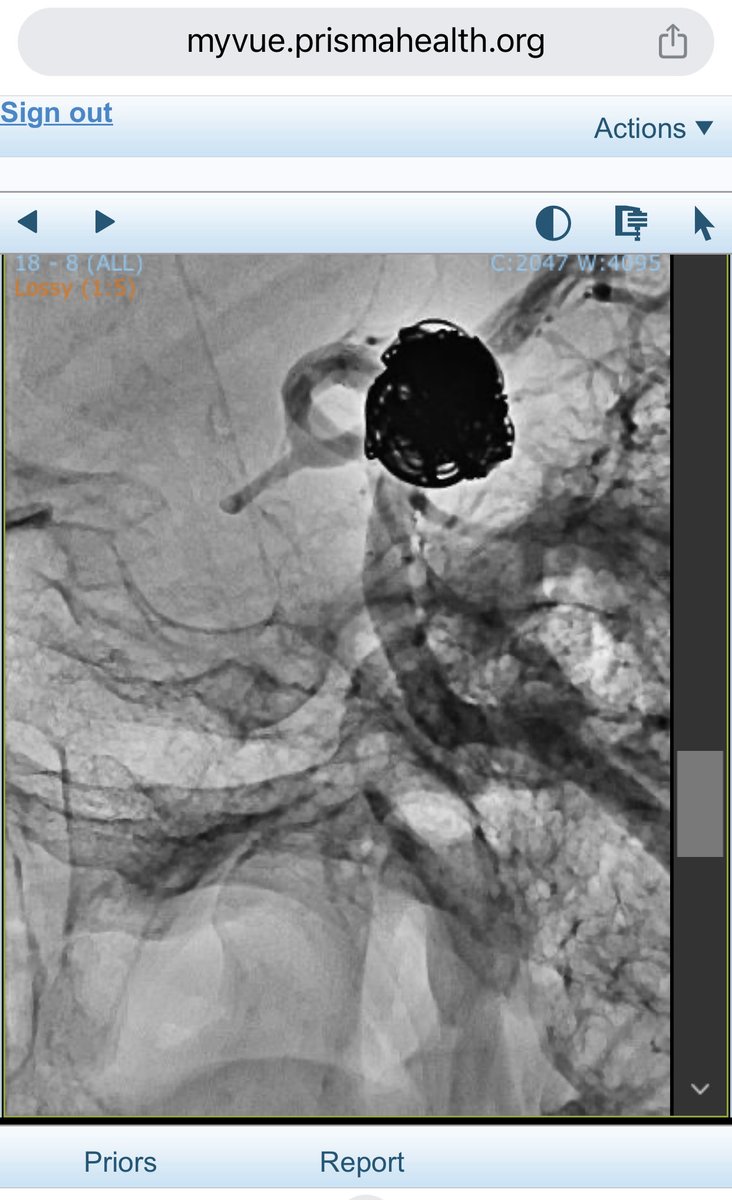

The last intracranial aneurysm embolized this year, 2025. I wish you a happy and prosperous New Year 2026.

New Case! 🎬 Sentinel headache and an Acom #aneurysm with a bleb - treatment using EVO stent assisted coil embolization using the EVO stent as a comaneci device for remodeling. Thoughts? @gustavomcortez; @jaims_lim; @UB_Neurosurgery; @terumoneuro ; @Stryker_NV